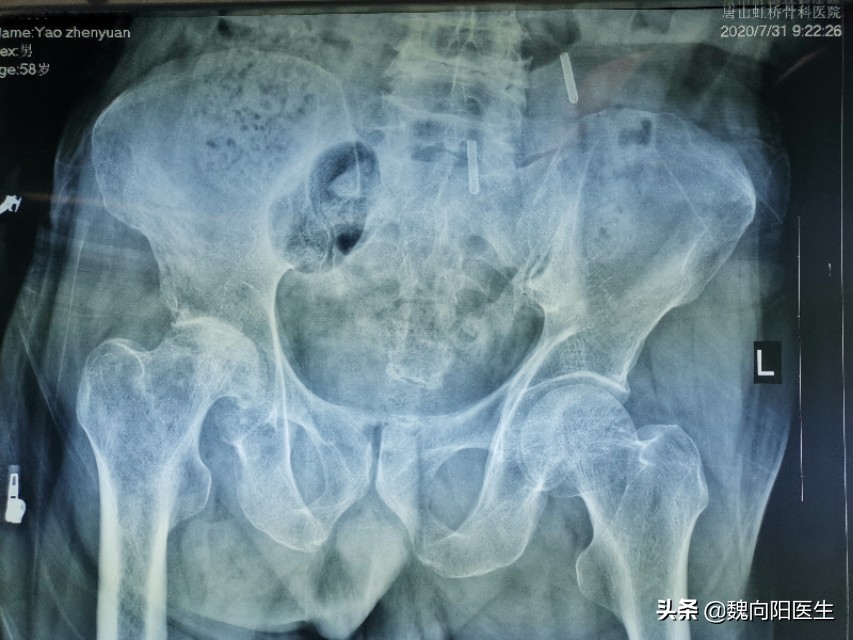

拍骨盆的x光片提示:右侧股骨头坏死,股骨头严重塌陷。

终于找到右侧膝关节疼痛的原因了,原来是骨头导致的“髋病膝痛”。